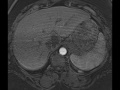

Hemangioma

Multiple MR images demonstrate a T2 bright hepatic mass which demonstrates peripheral, central, globular enhancement, compatible with hemangioma